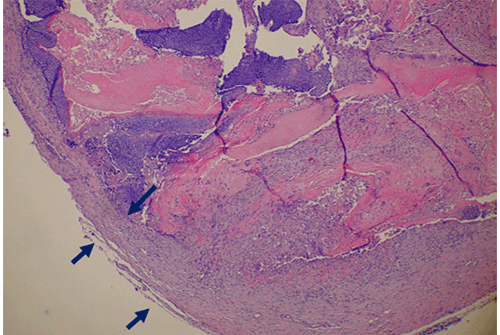

The patient tolerated the surgical procedure well without any perioperative complications. Pathologic examination revealed a formalin-fixed, 1.4 × 0.7 × 0.7 cm tan-red mass with a red-to-white, gritty cut surface. Histopathologic analysis demonstrated two distinct cell types: a basophilic cell type with mitotic figures and indistinct cell borders, and an eosinophilic cell type lacking nuclei and exhibiting more distinct borders. Additionally, multinucleated giant cells were noted within the surrounding tissue (Figure 3).

Figure 3. Histopathology of Excised Specimen (H&E Stain). Published with Permission

(A) Low-power magnification reveals a lobular, partially cystic lesion with a thick, fibrous capsule (dark blue arrows)

Histopathological hallmarks of PMC include islands of epithelial cells made up of basophilic cells, a transformation zone to eosinophilic shadow or “ghost” cells, and calcification.7,9,10,12 Additionally, studies have indicated that PMC tumors are often encapsulated in a thick layer of fibrous tissue.16,17 All of these histological markers except calcification were noted in our patient’s tumor (Figure 3).

The morphological progression of PMC is theorized to occur in stages. The first (“early”) stage is characterized by a small, cystic tumor. This progresses to the “fully developed” stage, with a larger, more cystic tumor and basophilic cells at the periphery. The “early regressive” stage is marked by islands of basophilic cells, shadow/ghost cells, and multinucleated giant cells. The final (“late regressive”) stage is characterized by a lack of basophilic and giant cells with calcification and ossification.18 Based on the histopathological findings, our patient’s PMC appears to have been in the “early regressive stage” at the time of diagnosis.